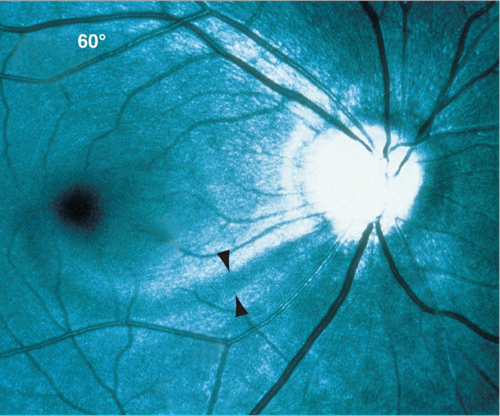

RNFL

You can actually see axons of the RNFL if you look carefully at the posterior pole - it can help to use the red-free filter to highlight the axons and areas of focal loss. A healthy nerve fiber layer appears as bright striations; focal loss of nerve fibers appear as dark bands; diffuse loss just looks like a sad, dark desert - usually in the superior and inferior poles relative to the nasal and temporal areas.